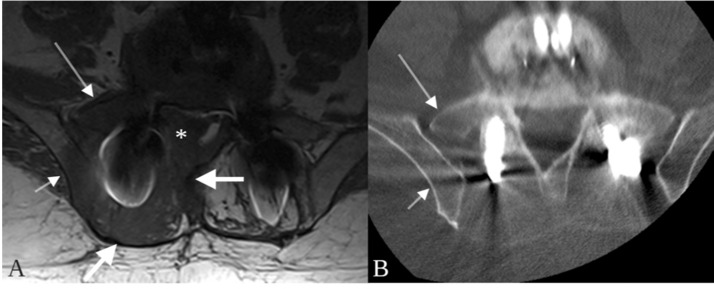

Fig. 1.

Metalloma surrounding a paraspinal rod at L4. The ovoid lesion (thick arrows) is nearly isointense to muscle on T1 (A) and T2-weighted imaging (D), and isodense to muscle on non–contrast CT (C). The mass does not enhance on post-contrast T1-weighted images (B) although a narrow margin of enhancement (B, thin arrow) is present in the right psoas muscle adjacent to the mass. The mass extends into the neural foramen and right extraforaminal space at L4 (D, asterisk).

Descriptions in the literature of imaging findings of spinal fusion-related metallosis and pseudotumors and/or metallomas are scant. This is likely due to rarity and due to hardware-related artifact that often obscures the region of interest on CT and MR images. Fortunately, in the case presented here, the large metalloma size allowed accurate characterization of the lesion on MR imaging. The metalloma in this case was a unique mix of both benign and aggressive imaging features. Trans-spatial involvement is a feature most commonly observed in aggressive processes such as malignancy and infection. In the featured case, the lesion was centered around the fusion construct in the paraspinal space and the associated T1 hypointense signal abnormality extended into adjacent bones (pedicles, iliac bone, sacrum) and soft tissues (epidural space, extraforaminal space, retroperitoneal space and/or psoas muscle), with seemingly no hinderance posed by the fascial planes that normally separate theses spaces (Fig. 1, Fig. 2). Mass effect is another feature concerning for an aggressive process that was seen in this case. However, the lesion appeared completely non–enhancing on post-contrast T1-weighted imaging – a feature more commonly associated with non–aggressive processes (Fig. 1). The combination of trans-spatial involvement and lack of contrast-enhancement may be a finding unique to metallomas. Additional imaging clues to the diagnosis in this case are the location of the lesion, which surrounded the fusion construct, and the T1 and T2 isointensity to skeletal muscle, which has been described with metallosis and pseudotumors involving metal-on-metal hip arthroplasties and may be related to T2 gradient recalled echo (T2 GRE or T2*-weighted imaging) effects of small metal particles [37].